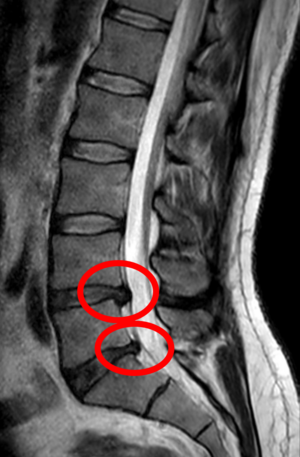

Pentru a înțelege modul în care terapia manuală și masajul pot preveni hernia de disc, să începem prin a înțelege ce reprezintă această afecțiune. Hernia de disc apare atunci când partea interioară a unui disc intervertebral iese prin stratul exterior și poate exercita presiune asupra nervilor spinali. Aceasta poate duce la dureri de spate, amorțeală, slăbiciune musculară și chiar pierderea controlului asupra vezicii urinare sau intestinelor.